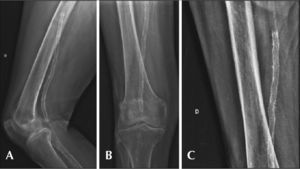

Postoperative follow-upThe follow-up was performed with outpatient evaluation, consisting of physical examination and ankle-brachial index (ABI) determination at 15, 30, 90, and 180 days after angioplasty. The control with Doppler ultrasound (USG-D) was performed at 30, 90, and 180 days after surgery, with the aim of identifying restenoses (Figure 3). Radiographs of the knee joint in posteroanterior (PA) and lateral views were performed at 30 and 180 days, with the aim of identifying stent fractures (Figure 4).

Ultrasonographic control at 6 months of stenting in the middle segment of popliteal artery. (A) Color-mode image without signs suggestive of stent fracture. (B) Color-mode image, showing laminar flow without vortices and no signs of neointimal hyperplasia. (C) Doppler Ultrasound demonstrating spectral curve of speed in native artery. (D) Doppler Ultrasound demonstrating spectral curve of intra-stent speed with a velocity of 70 cm/s and a speed ratio of 1.